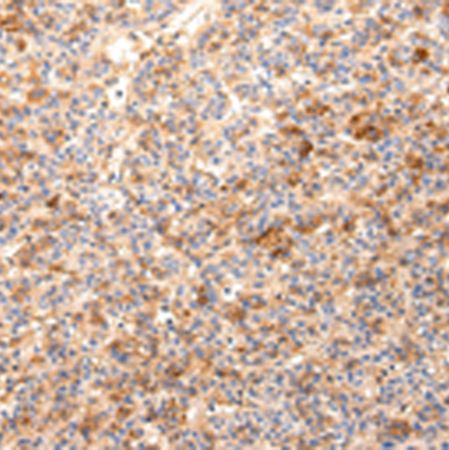

| Applications: | ELISA,WB |

| Immunogen: | SyntheticpeptideofhumanZNF365 |